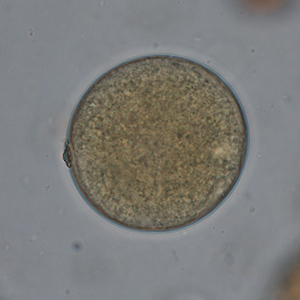

Le kyste est sphérique à ovoïde, à paroi épaisse, mesurant 50 à 100 μm de diamètre. Il présente un contenu granuleux, un macronucléus et micronucléus difficilement visibles (Strait et al., 2012). La coloration au Lugol permet de mettre en évidence certains organites qui apparaissent en brun sombre, de colorer la paroi en brun et l’intérieur du kyste en jaune.